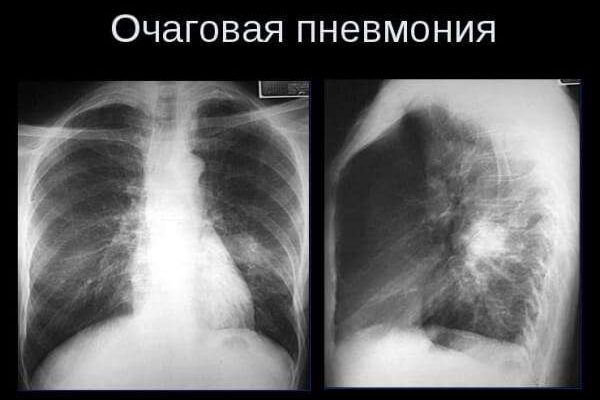

Очаговая пневмония (также известная как бронхиальная или бронхолегочная) — наиболее распространенная форма пневмонии, при которой инфекция распространяется на легочную ткань из бронхов и поражает небольшие участки легочной ткани — дольки легкого, которые включают альвеолы и прилегающие к ним мелкие бронхиолы. калибра. Этот вид пневмонии может развиваться самостоятельно или быть вторичным, осложняя другие респираторные заболевания. Очаги воспаления могут располагаться как в легких, так и в разных областях, но чаще всего в их нижних долях.

В зависимости от количества и размеров воспаленных участков в паренхиме легких различают крупноочаговые и мелкоочаговые пневмонии, очаги могут быть одиночными и множественными. Выраженность и продолжительность клинических симптомов зависят от размера и количества воспалительных очагов.

На снимках одиночные очаги воспаления чередуются с участками с эмфиземой, микрометастазами. Это самый тяжелый вид курсов. Клиническая симптоматика больше похожа на круповую пневмонию. Необходимо интенсивное лечение, желательно в больнице.